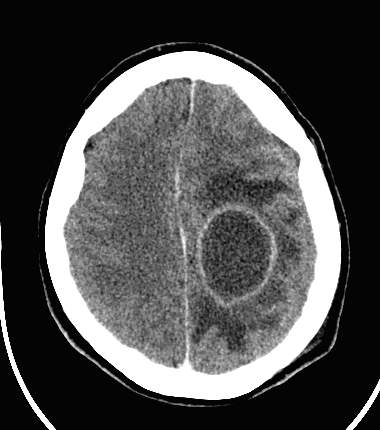

CT can usually lead to definitive diagnosis regarding brain tumors. A non-territorial localization (as opposed to arterial occlusion) of a usually “glove” shaped perifocal hypodense zone is highly suspicious for a tumor.

Contrast enhancement of tumors, specific forms of enhancement:

Therefore, where contrast enhancement is seen, the blood-brain barrier is damaged. This is only possible in intra-axial brain tumors, inflammatory states, certain types of demyelinating diseases (multiplex sclerosis) and at certain states in ischemic infarcts.

Contrast enhancement is usually round or it resembles a garland shape.

In more advanced stages of abscess development (“mature” abscess, early capsule phase) the central hypodensity deepens further, the rim of enhancement becomes better defined and thin. The multilocular appearance is also possible. A slight vasogenic edema is seen outside the enhancing rim of the abscess.